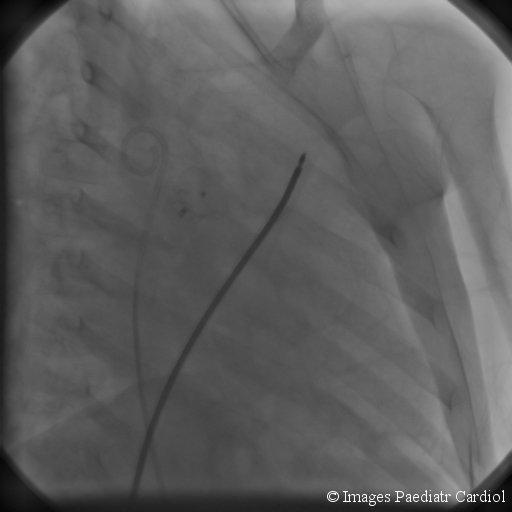

Nonsurgical closure of patent ductus arteriosus (PDA) using a duct occluder placed percutaneously is currently the first line of therapy and the success rate is quite high. Several devices are currently available. An eight year child underwent device closure of the ductus. However after deployment of the device it, became dislodged into the left pulmonary artery. Several attempts at catheter retrieval failed. The child underwent successful surgical removal of the device without cardiopulmonary bypass.

使用经皮放置的导管封堵器非手术闭合动脉导管未闭(PDA)目前是一线治疗方法,成功率相当高。目前有几种装置可供使用。一名8岁儿童接受了动脉导管的封堵器闭合术。然而,在装置植入后,它移位到了左肺动脉。多次尝试通过导管取出均失败。该儿童在未进行体外循环的情况下成功接受了手术取出装置。